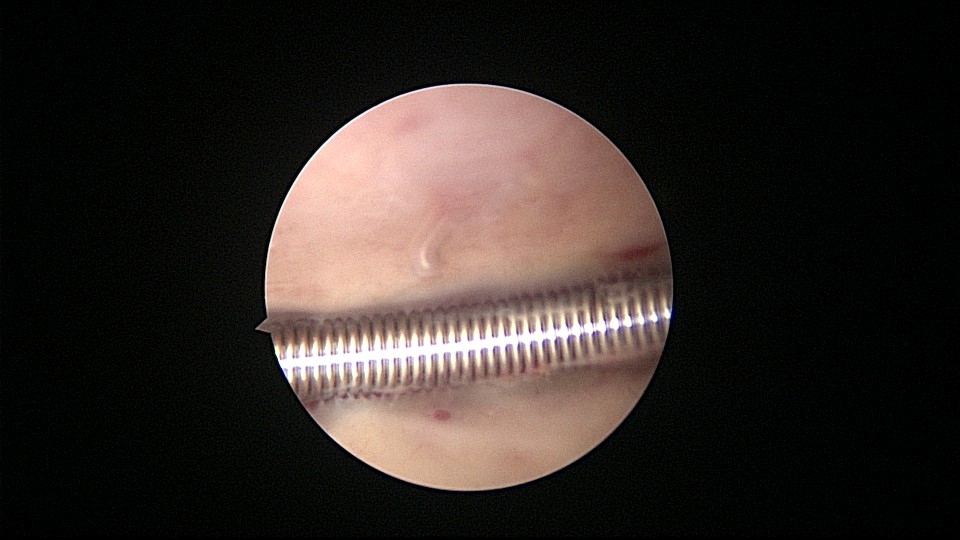

患者55岁,G1P1,顺产1次。安环34年,闭经半年,2天前外院取环失败,感下腹疼痛不适。术前复查B超,子宫前壁肌瘤直径4cm,宫内节育器回声。术中见子宫前倾后屈位,宫颈外口见息肉,镜鞘旋转扩宫进入宫腔,O型环位置正常,宫腔右前壁见直径2.5cm肌瘤结节突向宫腔,取环钩顺利取出节育环,宫腔无其他异常。该患者常规取环时未膨宫,子宫位置特殊,加之子宫受刺激后肌瘤凸向宫腔,可能对取环器械形成支点及杠杆效应,取环器械难以到达节育环位置,导致取环失败。